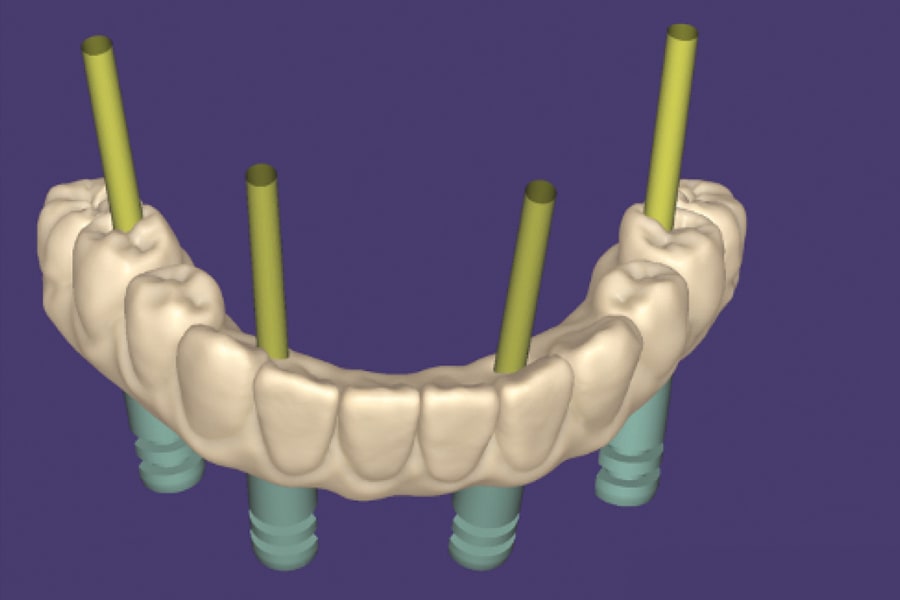

The provisional prosthesis also was designed using dental CAD software (DentalCAD, exocad, exocad.com) and 3D printed (Sonic Mini 4K 3D Printer, Phrozen, phrozen3d.com) with a nanoceramic hybrid Food and Drug Administration-cleared class II dental resin (OnX, SprintRay, sprintray.com). The provisional prosthesis was then post-cured (Procure 2, SprintRay) according to the manufacturer's instructions. Cylindrical spacers with dimensions of 6.3 mm x 6.3 mm were designed digitally at the tissue surface of the prosthesis for the titanium bases (ti-bases) pick-up.

The interim prosthesis was fabricated with buccal pins to engage the pin connectors on the bone reduction guide (Figure 8). The tissue surface of the prosthesis was relieved 3 mm from the crestal bone in the planning software to allow for soft-tissue thickness after the flap closure. Because the implant and MUA locations were predetermined, a spacer was already created under the prosthesis to pick up the ti-base on top of each MUA (Figure 8).22 With the bone reduction guide still in place intraorally, bite registration material was injected into the relieved areas of the tissue side of the interim prosthesis, which was seated onto the pin connectors intraorally (Figure 9). To accommodate any slight error during implant placement, a fast-setting polyvinyl registration material (Imprint™ Bite, 3M Oral Care, 3m.com) was used under the interim prosthesis to determine if any interference between the pick-up spacers and the ti-bases existed (Figure 10). Interferences were then marked under the interim prosthesis with a pencil and relieved using an acrylic bur.